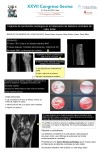

Primeros casos de artroplastia de interposición para el tratamiento de la artrosis escafotrapeciotrapezoidea en nuestro centro.

Guillermo Martinez Bovaira, Gemma Gazquez Gazquez, Isabel Cabanes Ferrer, Lorenzo Hernández Ferrando